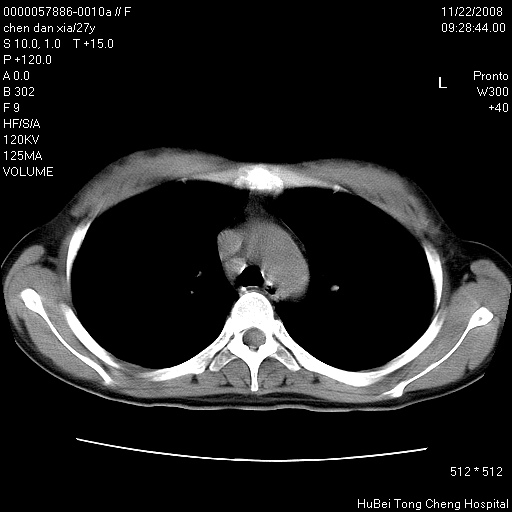

标题: CT16752:F,27Y。发热咳嗽20余天,伴盗汗。 [打印本页]

标题: CT16752:F,27Y。发热咳嗽20余天,伴盗汗。

考虑双肺粟粒性肺tb,右侧胸膜增厚.

右下肺见片絮状影,两肺野内分布不均的小结节影,结核并肺内播散可能性大,建议结合实验室检查 .

右侧前胸壁胸膜局限性肥厚(胸膜炎?)其他的强化观察.

以下是引用hyhxn在2008-11-22 18:02:00的发言:[br]考虑双肺粟粒性肺tb,右侧胸膜增厚.